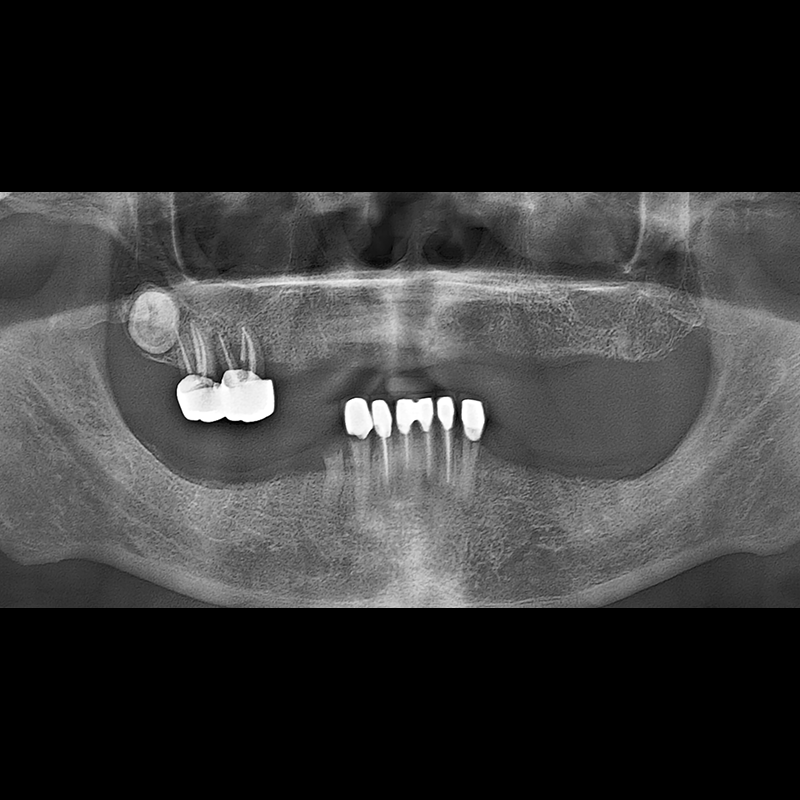

IMPLANT

BEFORE AFTER

Implant before and after 2025.05.30

Implants were placed in the missing tooth and in the tooth position where it was difficult to save.